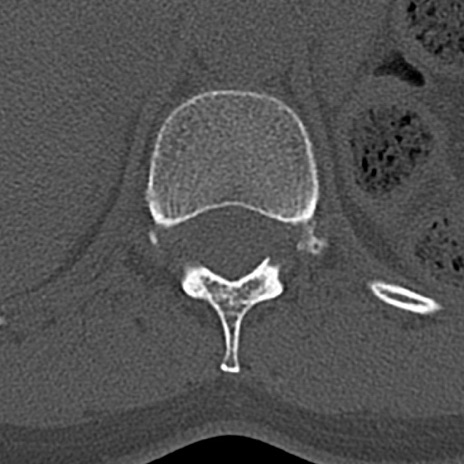

腰椎CT

横断像と矢状断像